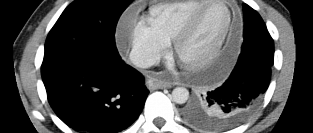

Сахарный диабет и скрининговая КТ-ангиография коронарных артерий. Обосновано ли использование?

Скрининг в отношении бессимптомного обструктивного атеросклероза коронарных артерий у пациентов с са...

15.12.2014 6374 #сахарный диабет #сахарный диабет 2 типа #КТ-ангиография